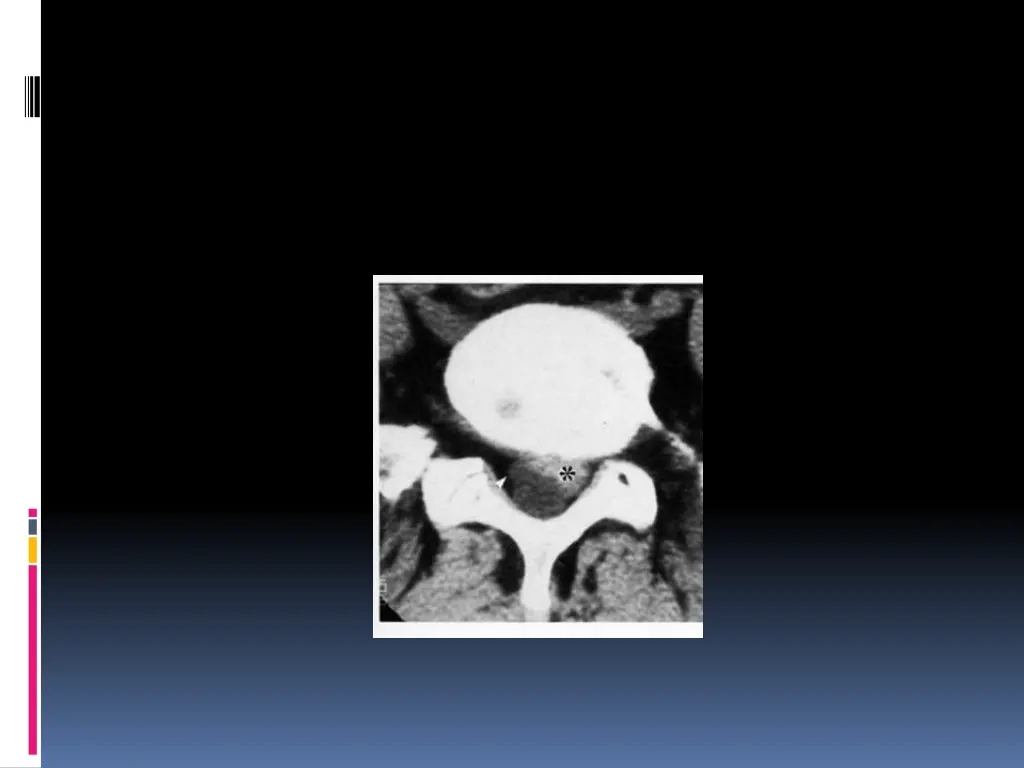

SCANNER: Visualise la hernie, sa situation, son importance et la surface utile du canal rachidien. Coupes millim triques sus et sous-jacentes l espace discal v rifient l ventualit d une migration et son importance L IRM: Si la TDM ne d c le pas la hernie Si r cidive apr s CHX My lographie ou saccoradiculographie EMG